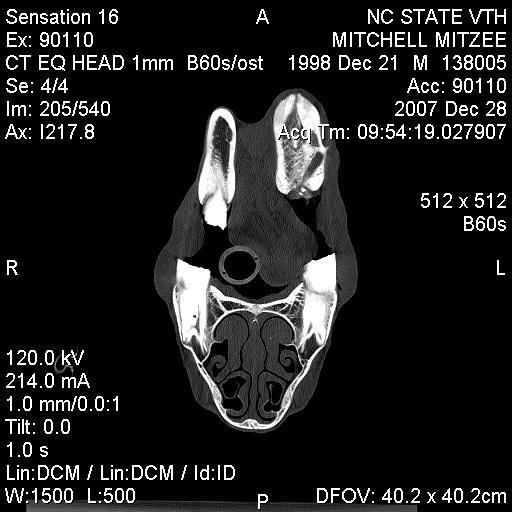

Posted on Sunday, Jun 24, 2007 - 3:39 pm: Greetings Everyone,I have finally received some of Mitzee's xrays, though it appears that I'm missing several... hmmm... Anyway, I thought I would give everyone an update. After two weeks of inpatient care (IV antibiotics, anti-inflamatory agents, a few different wound site I&Ds, several xrays and another fistulogram, etc...), she was discharged on 6/7/7. The final fistulogram showed NO evidence that the draining sinus tract communicated with the adjacent tooth root (4th premolar), but, rather, seemed to travel to the empty alveolar socket of her previous surgical site (the removed 3rd premolar). I had decided I did not want to attempt to manage her on my own, so I arranged to board her and Rorie at a facility owned by an equine vet, kind of like a lay up hospital situation... She's been getting daily assessment and care of her wound, the barn has a great fly control system and, so far, she usually goes out at night and stays in during the hot day. Plus, when she and Rorie are out, they're with other mare/foal pairs and that's a nice bonus for Rorie. Mitzee's eating well, her weight is good, and her activity is normal. And, though tissue healing is occurring, significant swelling of her left submandibular area persists and there are two remaining tracts that drain purulent material, though it is less than previously observed. I have decided to see how things go for awhile and "embrace" this conservative approach... clearly, the surgeon was not interested in pursuing more surgery at the time of her discharge, though when I corresponded with him recently (and showed the same pictures I am posting below) he suggested we get a CT scan. Of course, a CT scan appears to require general anesthesia and I would have to take her to a larger referral, probably academic, center. Based on where I am in VA, the closest facilities are NC State in Raleigh, NC, Marion duPont Scott in Leesburg, VA, or VA Tech in Blacksburg, VA... I do still worry that there's something "left behind" in the wound, perhaps a necrotic bone fragment???, that is continuing to feed this low level infection... At this point in time, she is almost 6 weeks postop from her initial surgery to remove premolar #3... Rorie was 8 weeks old last Tuesday... What does everyone think???? Thanks! Martha

Posted on Tuesday, Jan 1, 2008 - 11:08 pm: Hey Everyone,Sorry for the delay in posting the images... Mitzee was discharged on Sunday (POD 2) and I DrOve down to NC, picked her up, and travelled back to VA in the worst pouring down rain (not complaining, we still do have DrOught conditions a bit...) Anyway, I was on call the next day (New Years eve) and had a killer night, so I am still kinda brain dead today... I've managed to crash my laptop several times with the disc I was given at NC State... just wondering if it has anything to do with my new laptop OS, Vista, but now, finally, I've managed to load some of the study pictures onto my old laptop (hopefully the keyboard won't quit like it did this summer). The plain xray is not great... possibly me altering it in the download process??? Anyway, it is a lateral so you see both sides of the jaw and you have to focus on the near structures (the left side), not the far ones (the right side); basically, it shows distortion of the the left lower premolar #2, which has occurred following removal of #3 last May, and compensatory changes in the left upper arcade (see the big ramp/points above). The few CT views I've uploaded show extensive bony proliferation and periosteal reaction of the left hemimandible, an absent left lower 3rd premolar tooth, as well as some radioopaque densities below this area, presumed to be ?tooth fragments or cement debris following the previous surgery; there is one particular linear density located in the center of this area that was felt to represent a possible "sequestrum" and was removed... also, you can see a radiolucent tract that exits the lower portion of the left hemimandible below the empty alveolar area of the absent 3rd premolar. A lytic lesion is seen associated with the lateral aspect of left lower 4th premolar near the gingival margin and another draining tract travels between this front/rostral portion of the left lower 4th premolar tooth and the lateral aspect of the mandible; my discharge papers state that the CT findings "are consistent with peridontal abscessation and a draining tract", however the surgeon believes the root and pulp of the left lower 4th premolar tooth are still healthy, so we may have a ?50/50 chance of saving that tooth. I have also attached a few other pictures of Mitzee undergoing her CT scan under general anesthesia, her recovery from GA, and a view of the her face following the surgery where the diseased areas were debrided. Her discharge papers note the final diagnosis as "chronic osteomyelitis of the left mandible and peridontal disease adjacent to left mandibular premolar tooth #4". I'll keep everyone posted on her recovery. Thanks!!! Martha

Posted on Monday, Jan 7, 2008 - 4:56 pm: O.K., I am going to try and load the CT images again... please refer to my descriptions of them above. Also, the surgeon from NC State called me today and reported the results of the cultures taken during surgery; Mitzee has grown two types of anaerobic, gram negative rod bacteria, a Prevotella "species" and Fusobacterium nucleatum. He said that he had not had a Prevotella isolated from equines in the past, but that the Fusobacterium is a common oral bacteria in a number of species.... Now, the plan had been for Mitzee to receive two weeks of postop antibiotics, trimethoprim/sulfamethoxazole (Bactrim DS) and when I brought her home on POD#2, I was able to give her the PM dose by syringing paste directly into her mouth (she did protest a little); for the next 24 hours, I was on call and during my absence the barn staff failed miserably in getting any drug into her! I certainly didn't want any of the barn staff to sustain injuries, nor did I want Mitzee to be hurt (apparently, she got into her rearing mode...), so I spoke with the surgeon then and he said I could forego her oral antibiotics (afterall, the surgical debridement was the "definitive" therapy!). Today, he mentioned that metronidazole (Flagyl) was the typical antibiotic for anaerobes, but that horses tolerate it even less than the Bactrim she had been on... so, since he felt good about the debridement, we are not treating her with antibiotics. The plan is to (as long as she looks good "clinically") take her back to Raleigh in about 4 weeks so he can examine her oropharynx and HOPEFULLY see that her orocutaneous fistula is HEALED and that the left lower premolar #4 is still O.K.!!! I'll keep everyone posted!Martha P.S. Keep in mind, when looking at the scans below, you are looking at a "cross-section" or axial image of the head, UPSIDE down... remember that she was laying on her backside to undergo the scan... also, the right side of the image is Mitzee's left side... notice the dramatic difference between the two sides, i.e., each hemimandible...